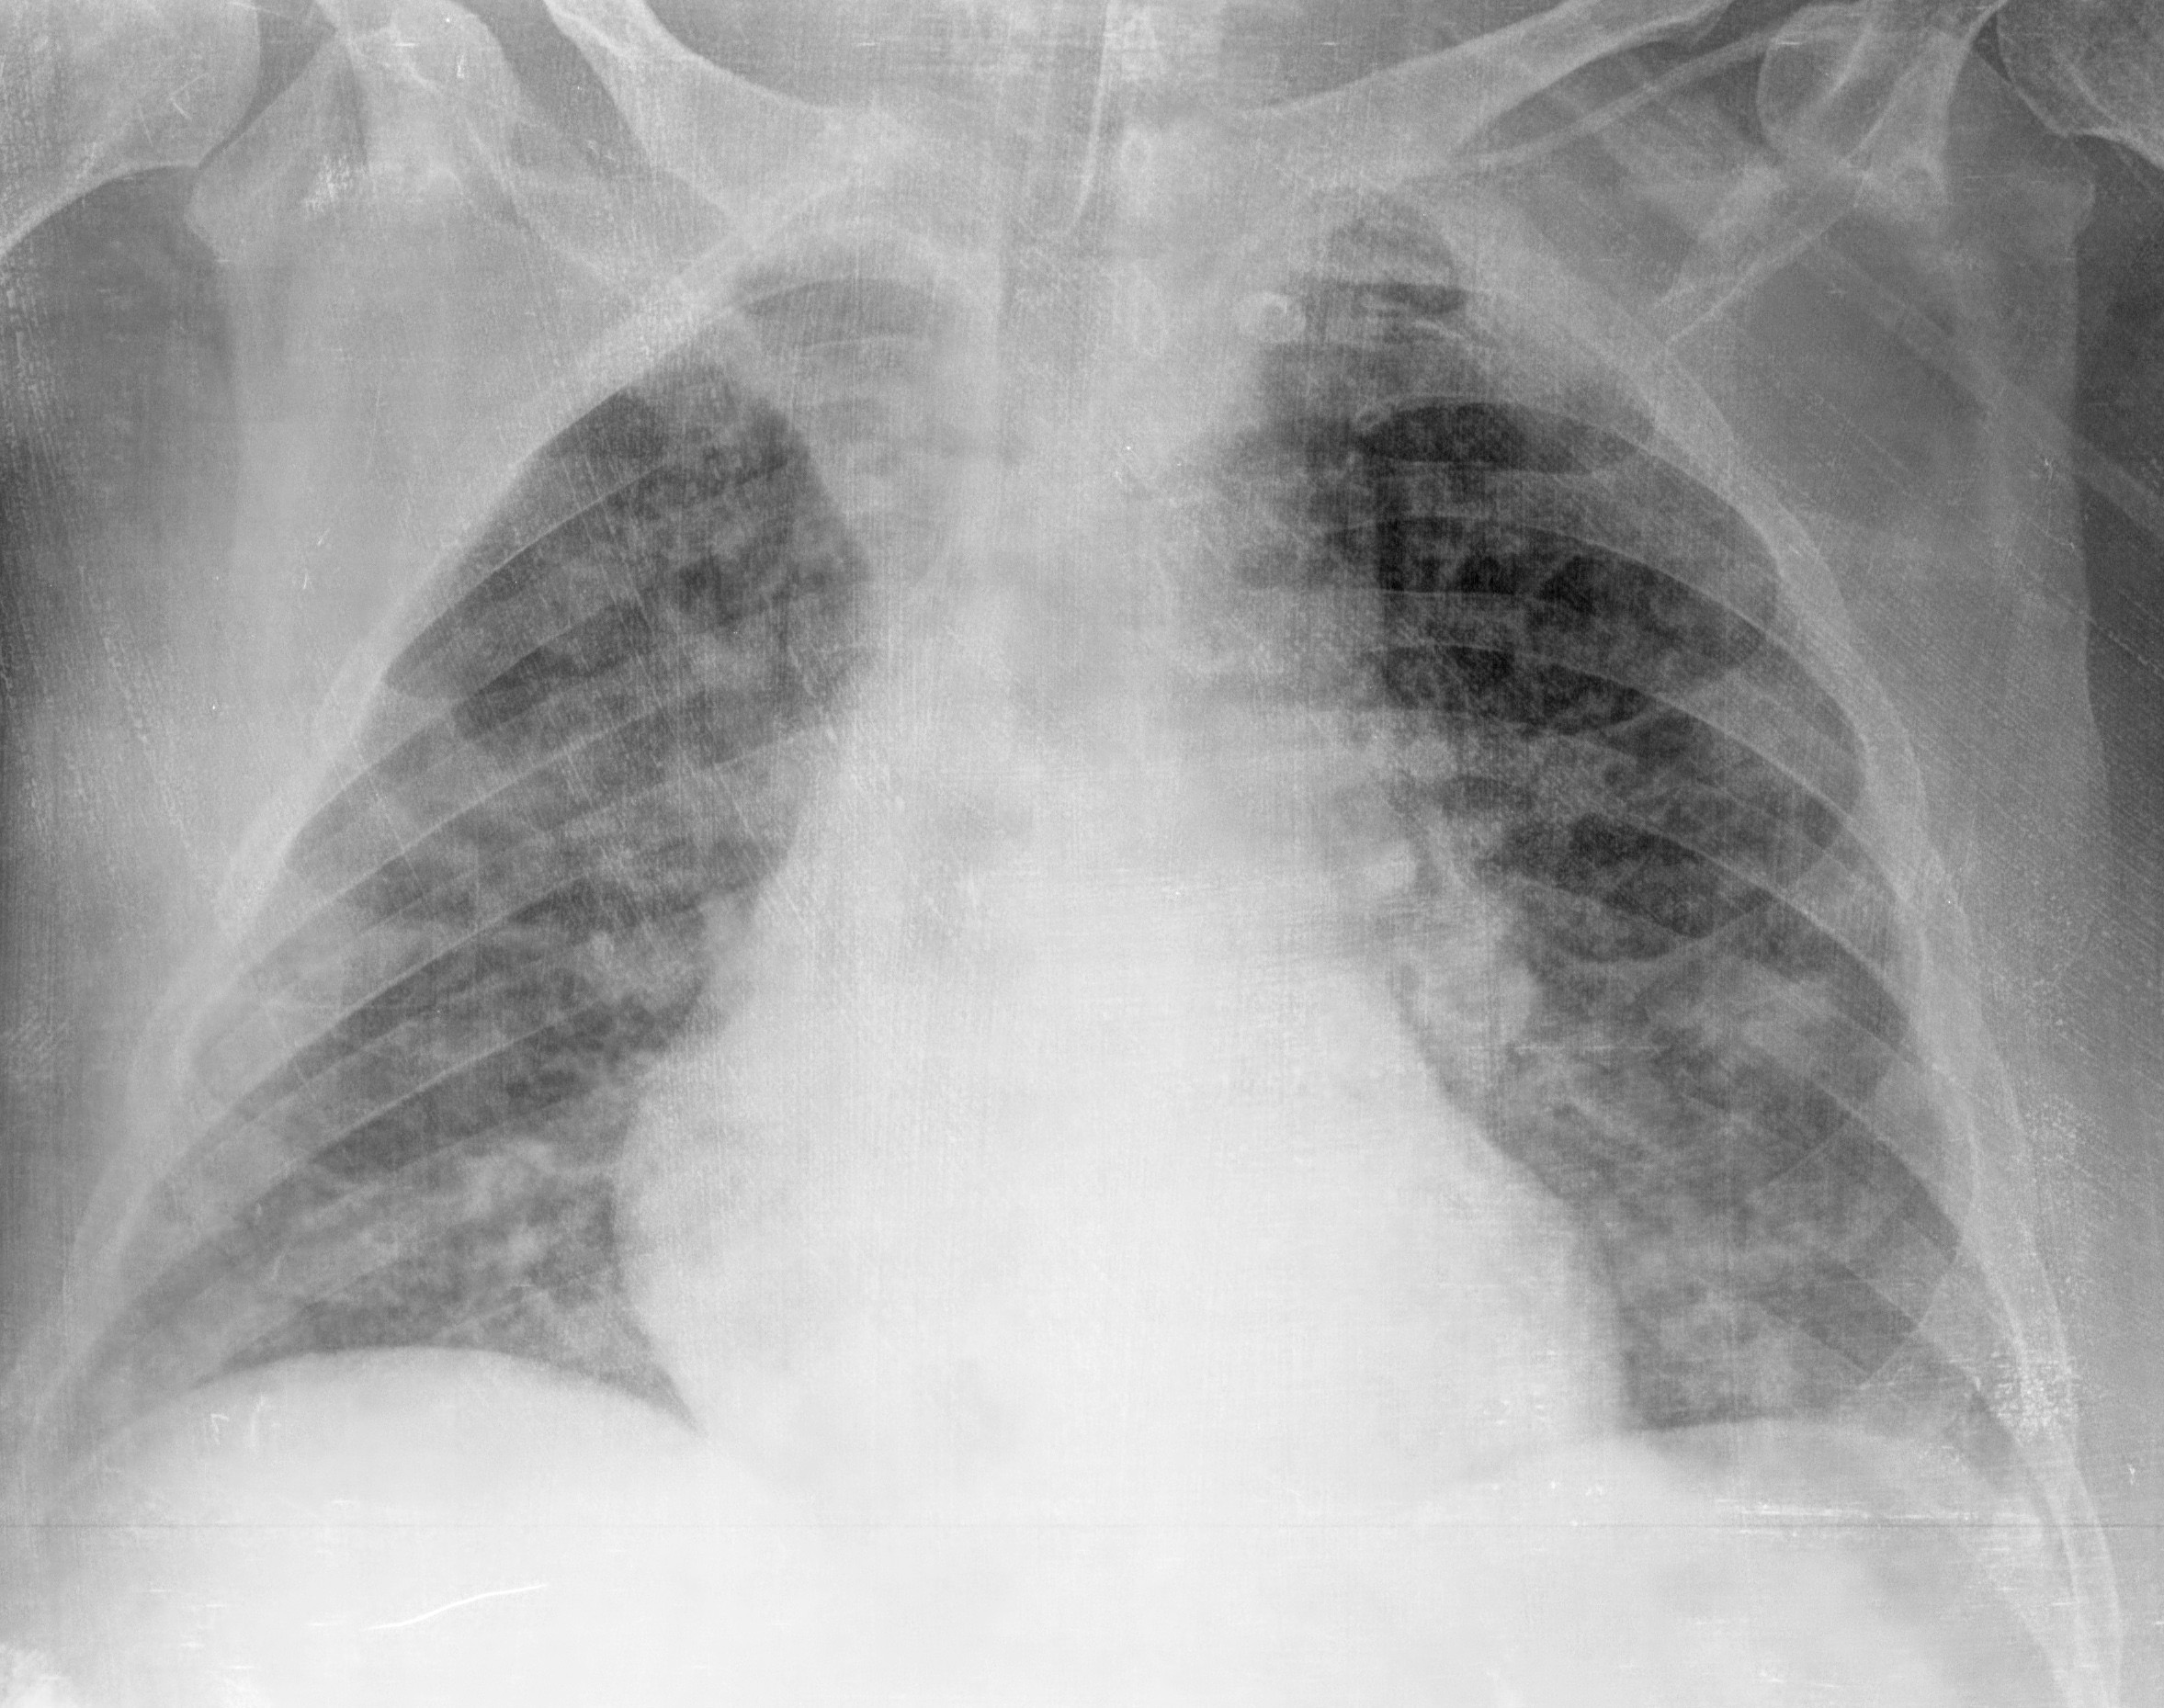

Paciente masculino de 70 años de edad con EPS asociada a artritis de cadera derecha por Staphylococcus aureus meticilino-resistente.La embolia pulmonar séptica (EPS) se define como la presencia de trombos sépticos en la circulación pulmonar provenientes de un foco infeccioso extrapulmonar. La obstrucción del flujo en vasos de pequeño calibre (secundaria a la presencia de émbolos infecciosos en la luz del vaso), puede condicionar el desarrollo de infartos y abscesos pulmonares.Las entidades asociadas a EPS son de naturaleza variada e incluyen: infecciones asociadas a dispositivos intravasculares, endocarditis infecciosa, abscesos hepáticos, infecciones en piel y tejidos blandos, tromboflebitis séptica, síndrome de Lemierre e infección periodontal. Los microorganismos aislados con mayor frecuencia son: cocos gram positivos (Staphylococcus aureus, Staphylococcus coagulasa negativo, Streptococcus spp.) y bacilos gram negativos (Fusobacterium, Klebsiella pneumoniae).Las manifestaciones clínicas de EPS son inespecíficas (fiebre, disnea, tos, dolor torácico pleurítico y hemoptisis).Las alteraciones en los estudios de imágenes son esenciales en el diagnóstico de EPS.En la radiografía de tórax de pacientes con EPS se describen opacidades nodulares, consolidación, lesiones cavitadas y derrame pleural.La tomografía computarizada (TC) es la imagen de mayor utilidad en la valoración de pacientes con sospecha de EPS. Las manifestaciones de EPS en TC se describen en la Tabla 1.